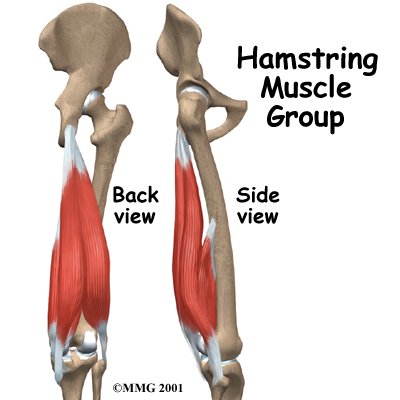

The hamstrings make up the bulk in back of the thigh. They are formed by three muscles and their tendons. The hamstrings connect to the ischial tuberosity, the small bony projection on the bottom of the pelvis, just below the buttocks. (There is one ischial tuberosity on the left and one on the right.) The hamstring muscles run down the back of the thigh. Their tendons cross the knee joint and connect on each side of the shinbone (tibia).

The hamstrings function by pulling the leg backward and by propelling the body forward while walking or running. This is called hip extension. The hamstrings also bend the knees, a motion called knee flexion.

Most hamstring injuries occur in the musculotendinous complex. This is the area where the muscles and tendons join. (Tendons are bands of tissue that connect muscles to bones.) The hamstring has a large musculotendinous complex, which partly explains why hamstring injuries are so common.